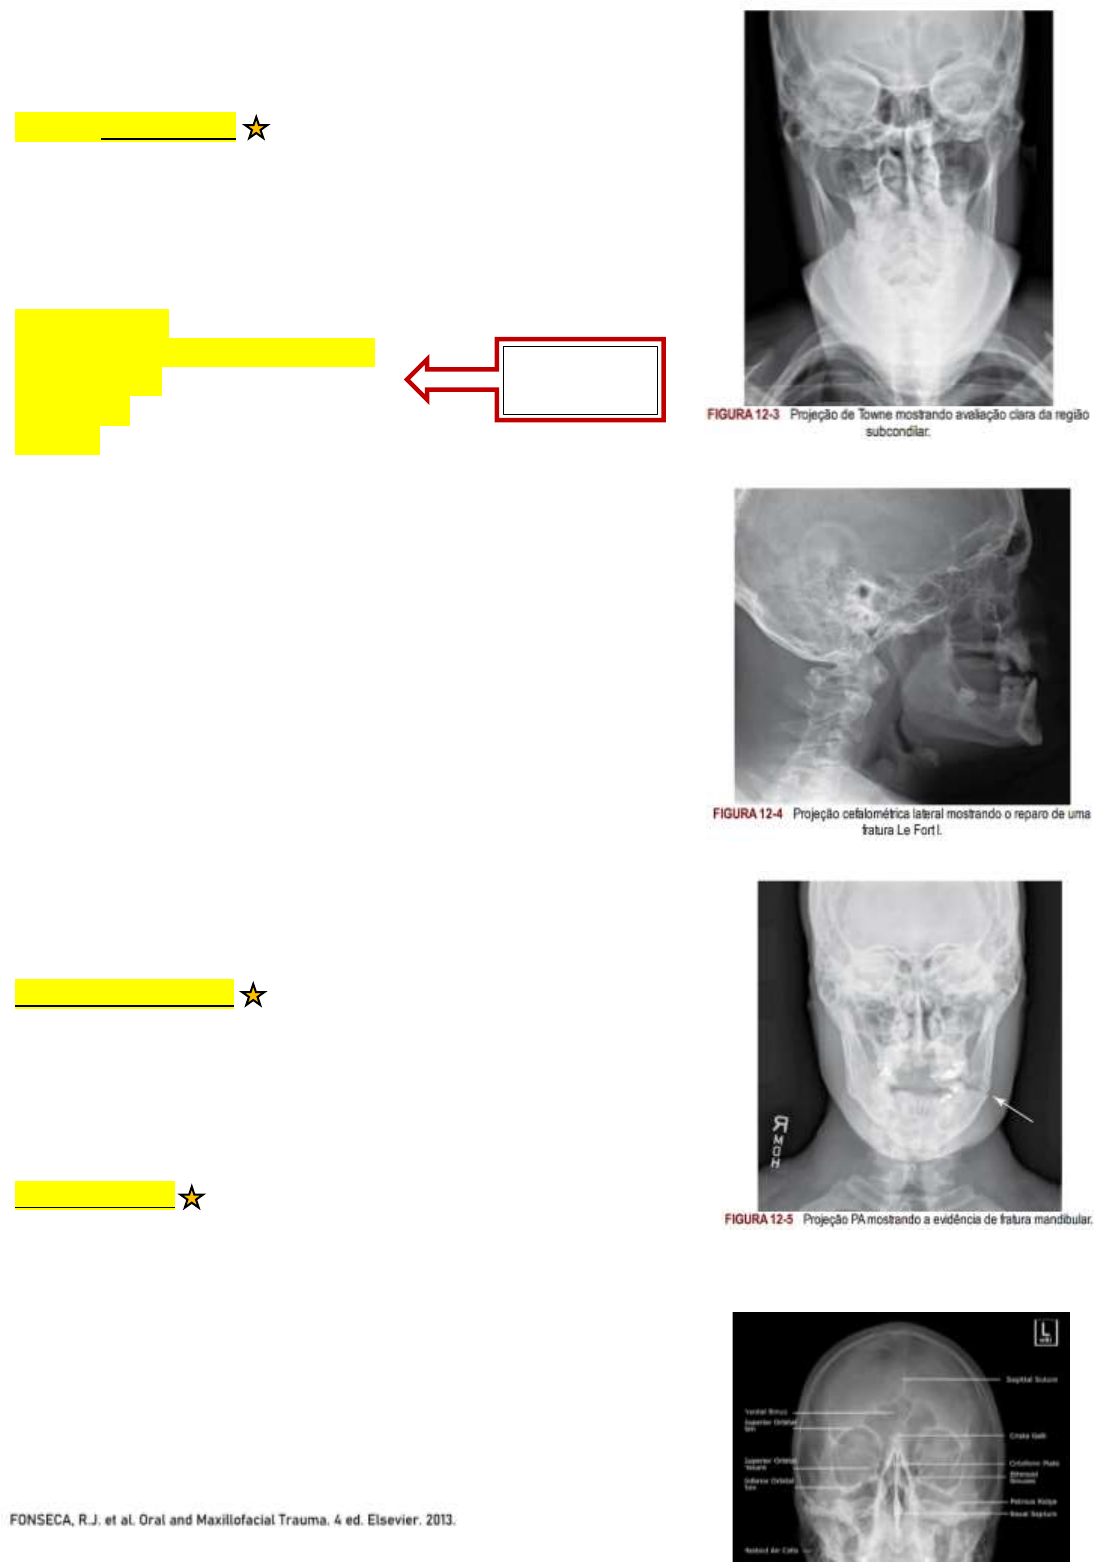

1. Incidência Radiográfica de Towne

ANGULAÇÃO MEDIAL/LATERAL E DESLOCAMENTO CONDILAR

- Fraturas subcondilares

1.1 Incidência Radiográfica de Towne Reversa

OBTIDA EM ANGULAÇÃO PÓSTEROANTERIOR (PA)

- Cristas petrosas

- Espaços pneumatizados do mastoide

- Forame magno

- Sela Túrcica

- Occipital

2. Radiografia Cefalométrica Lateral

3. Radiografia PA de face

- Fraturas do terço médio

- Fraturas mandibulares

4. Radiografia Caldwell